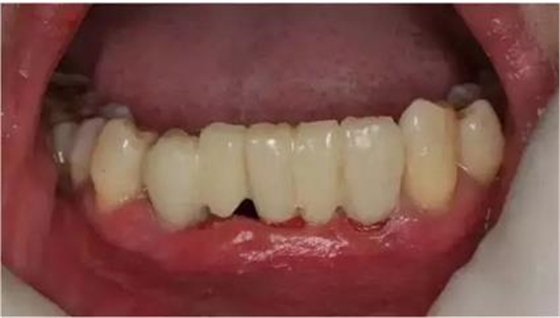

初診時(shí)下前牙不良修復(fù)體

臨時(shí)冠就位,即刻修復(fù),無咬合接觸